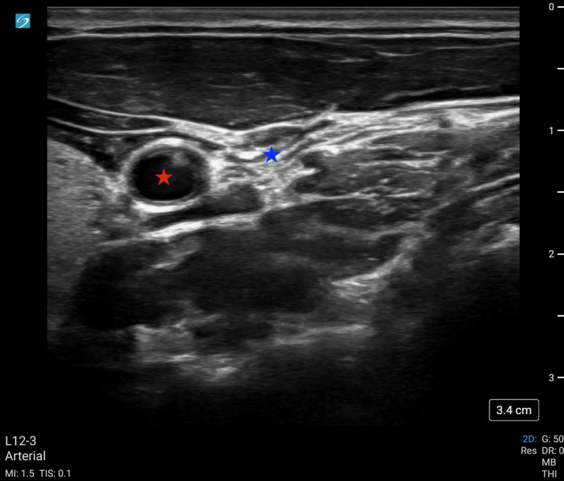

May2025Sonographic Fig 1 pocus cac.pngImage 1: POCUS-CAC with a fully compressed IJ (blue star) without compression of the common carotid artery (red star).

Video 1: POCUS-CAC showing complete collapse of the IJ with pulsatility of the adjacent carotid artery.